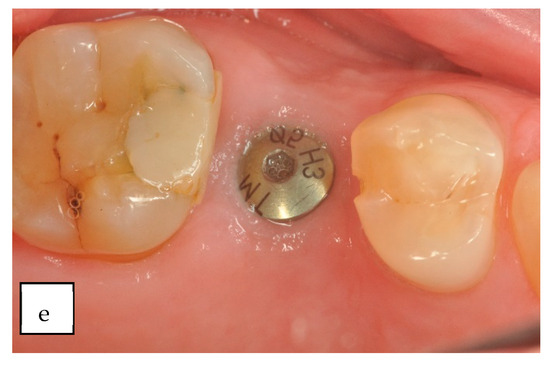

| Wachtel 2003 EHI 1–2 s | |

| Full closure |

| Incomplete closure |